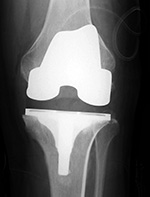

Stryker Triathlon PSC total knee arthroplasty

| There is a postoperative drain and skin staples. From Taljanovic, 2005 |

There is also a surgical drain and skin staples in place. 65 year-old woman. |